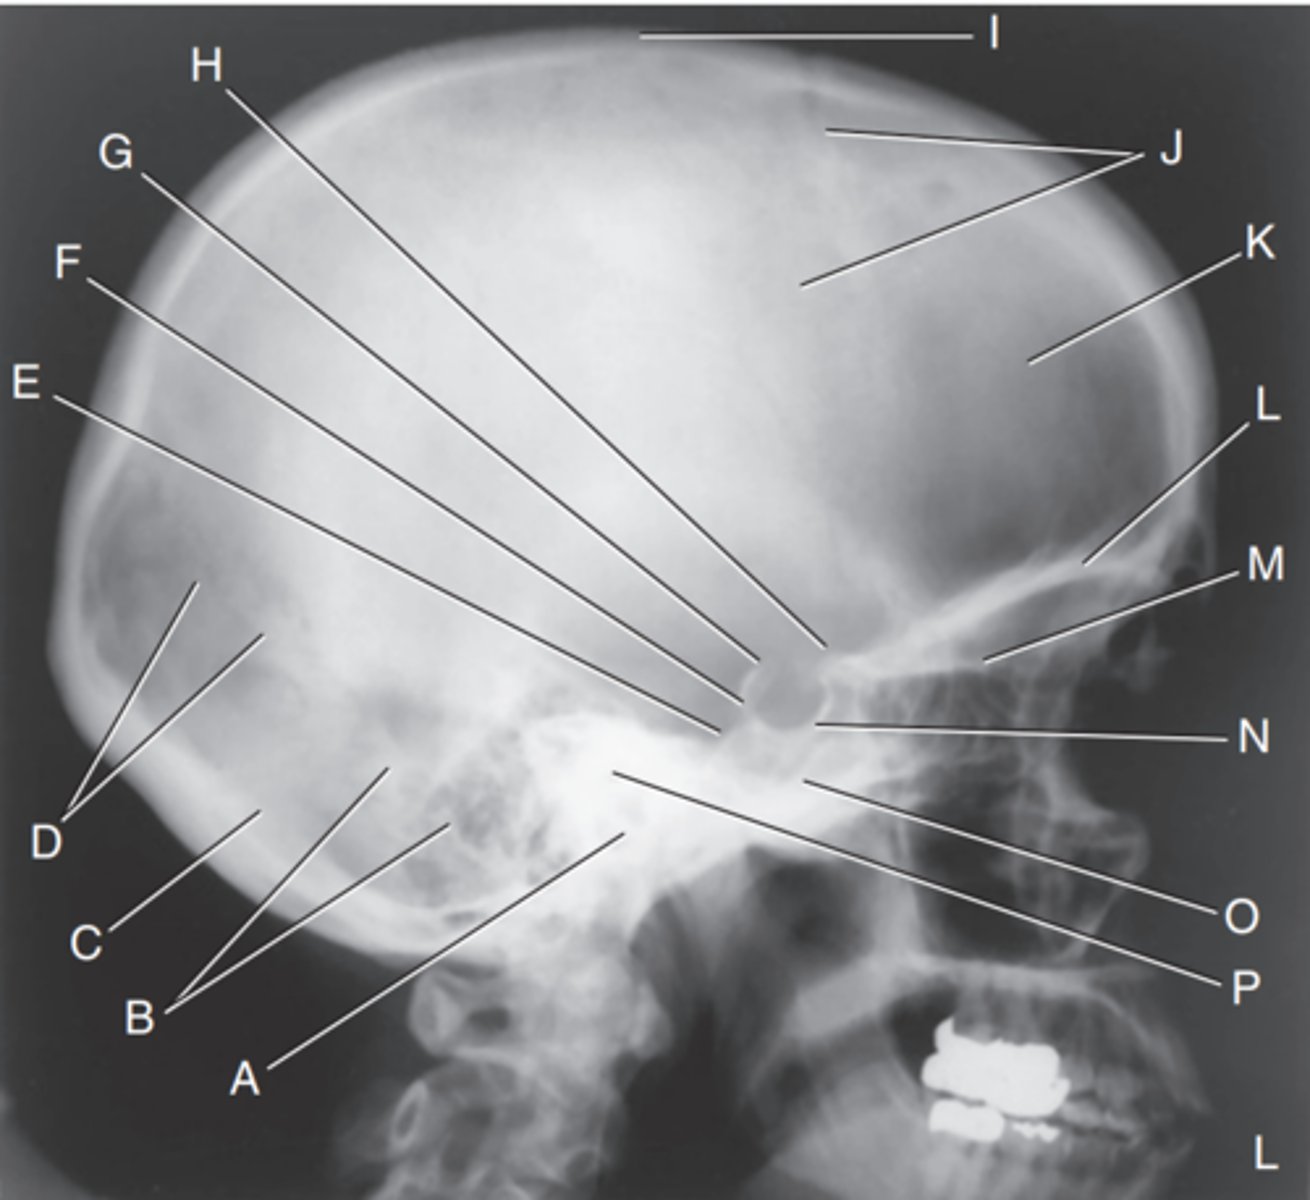

EAM

Label A

Mastoid portion of temporal bone

Label B

Occipital bone

Label C

Lambdoidal suture

Label D

Clivus

Label E

Dorsum sellae

Label F

Posterior clinoid processes

Label G

Anterior clinoid processes

Label H

Vertex of cranium

Label I

Coronal suture

Label J

Frontal bone

Label K

Orbital plates

label L

Cribriform plate

Label M

Sella turcica

Label N

Body of sphenoid (sphenoid sinus)

Label O

Petrous portion of temporal bone

Label P